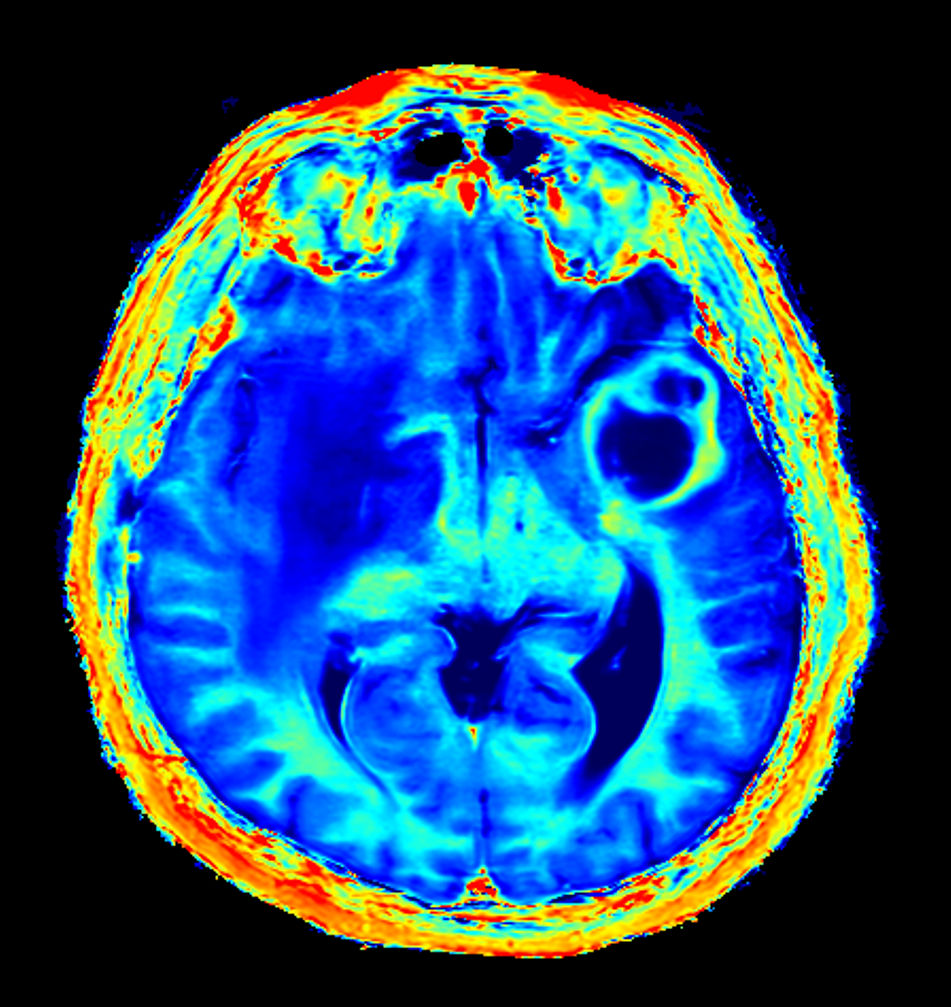

Patient with a large brain lesion. AI based SmartSpeed is utlized to shorten scan time without compromise in image quality. Advanced imaging techniques like pCASL and 3D APT are used to perform contrast-free brain imaging to assess perfusion and tumoral activity. SWIp 3D susceptibility weighted offers the high sensitivity required to visualize deoxygenated (venous) blood or calcium deposits. A single synthetic (SyntAc) brain quantification scan is added. The resulting data of this scan can be used as input for advanced third party processing software* to synthesize MR images with different contrasts, brain parenchyma fraction maps and/or brain segmentation maps.

Axial SyntAc (T1 Map)

Axial SyntAc (T2 Map)

Axial SyntAc (PD Map)